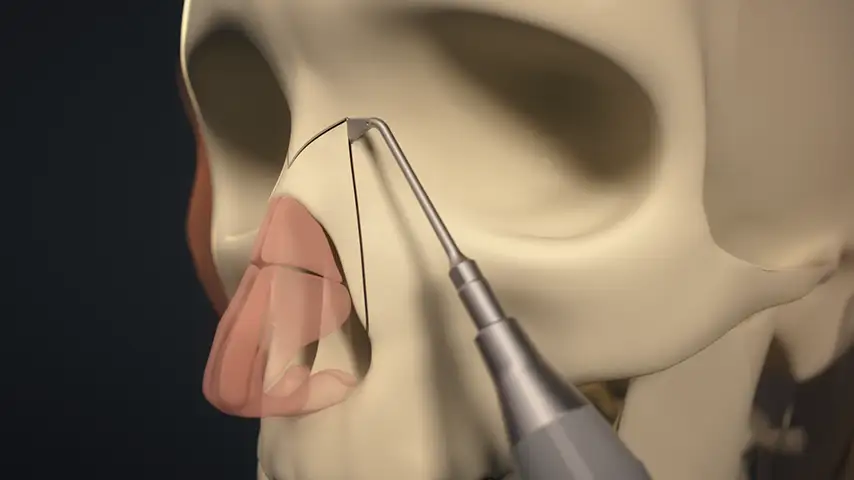

Clinical Applications of PIEZOSURGERY® technology

in Rhinoplasty

Hump takedown and dorsum modeling

Lateral osteotomy of nasal bone

Transverse osteotomy of nasal bone

Drilling of septum for suture fixation

Details

The finest and angled insert for insertion in limited space;

ideal for perforating nasal bones as well as ethmoid lamina splints.

Recommended insert:

Advantages over traditional tools

Reduced risk of damaging anatomically complex regions

Greater intraoperative control and bone management

Micrometric cut for minimal bone loss

Reduced heat generation to avoid bone necrosis